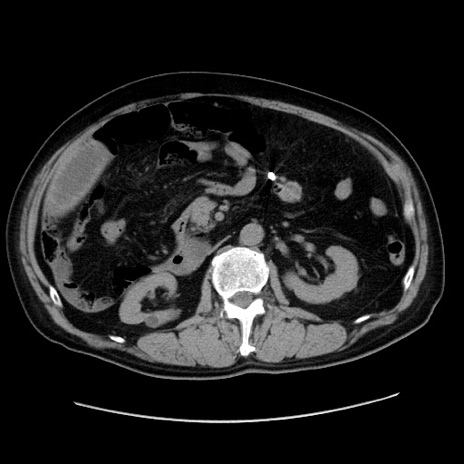

症例30(横断像)

【症例】80歳代男性

【主訴】臍周囲痛

【現病歴】約6時間前から臍下部痛が出現。次第に腹部膨隆・背部痛も生じてきたため来院。背部痛の場所は変化しない。

【身体所見】意識清明、BT 36.3℃、BP  131/87mmHg、P 87bpm、SpO2 100%(RA)、臍周囲自発痛・圧痛あり、反跳痛なし、自発痛部位に一致して板状硬あり、腹部膨隆、腸雑音減弱、CVA tenderness両側陰性。

【データ】WBC 19600、CRP 0.33